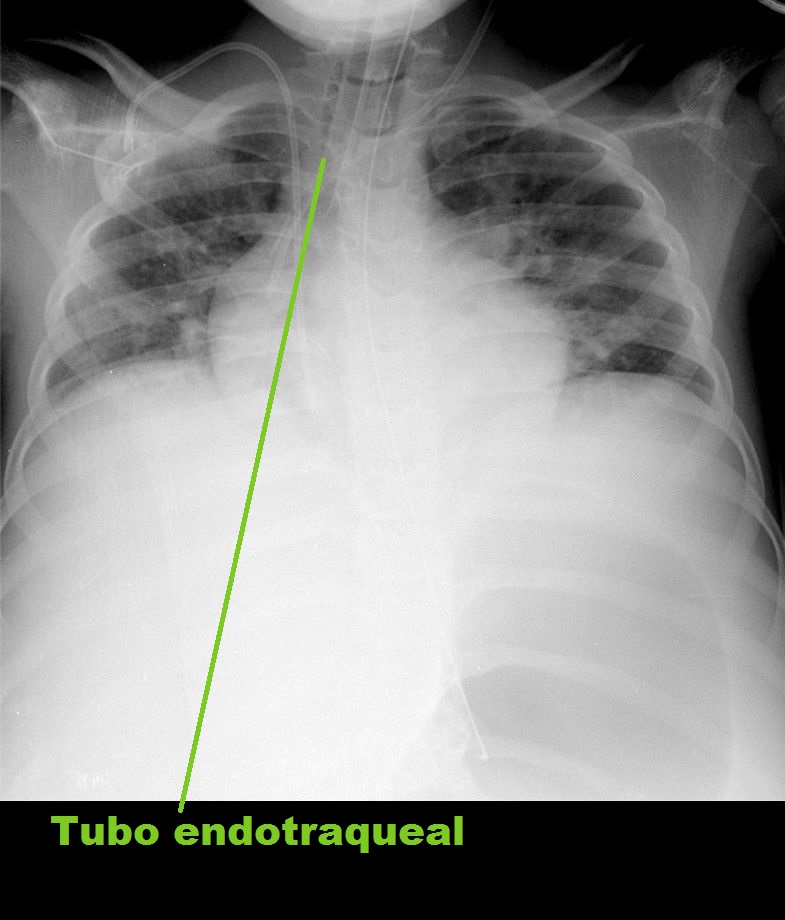

El tubo endotraqueal debe ubicarse a 1,5 cm de la carina, con el paciente en posición neutra, ya que esta localización puede estar modificada por el movimiento de flexoextensión de la cabeza.

• Tubo endotraqueal